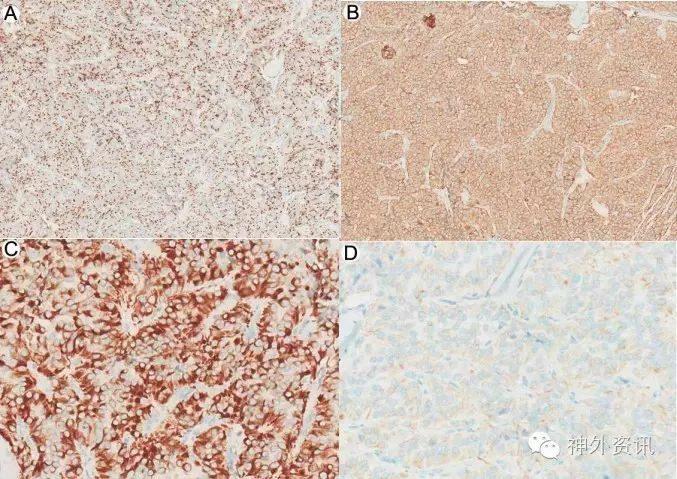

术后常规病理及免疫组化,报告为椎管内神经内分泌肿瘤,考虑转移性可能(图3)。免疫组化结果:S-100局部 +,GFAP-,Syn+,CgA+, CD56+, Vimentin+, NSE+, CAM5.2+, EMA -,Ki-67 10-20%,NF -, inhibin-, CD10-(图4)。

图4. 免疫组化结果: A.CGA弥漫阳性 B.SYN弥漫阳性 C.CAM5.2弥漫强阳性 D.CK(AE1 AE3)弱阳性。

由于该患者临床体征及检查结果未发现转移性肿瘤相关证据,病理诊断有待进一步明确,逐请美国UCLA进行神经病理联合会诊。UCLA结果报告为椎管内副神经节瘤,WHOⅠ级,免疫组化及相关结果见图5。